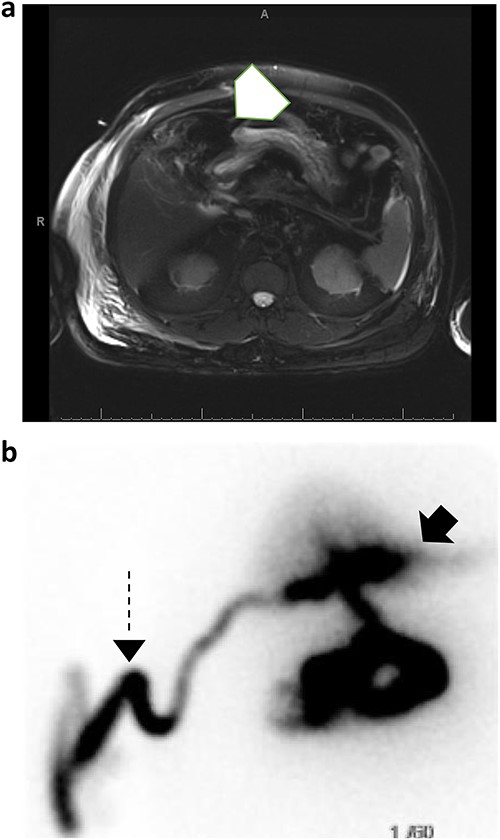

A 56-year-old male presented with a four-day history of right upper quadrant abdominal pain. One week prior to presentation, he underwent elective laparoscopic cholecystectomy at an outside hospital where his immediate postoperative course was complicated by a penicillin allergy reaction requiring ICU level care. Upon presentation to the emergency department labs were significant for mild leukocytosis of 11.1 K/uL with neutrophilia. Lipase and liver function tests were within normal limits. CT abdomen and pelvis showed a complex fluid density and foci of gas occupying the gallbladder fossa with concern for biloma or abscess (Fig. 1).

CT abdomen and pelvis with IV contrast demonstrating a complex fluid density with gaseous foci occupying the gallbladder fossa and measuring 6.5 cm × 5.8 cm × 5.5 cm.